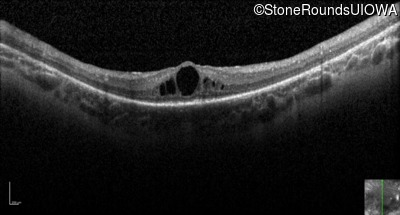

Optical Coherence Tomography - Left - 20/80 +2

Exemplar / OCT Stack